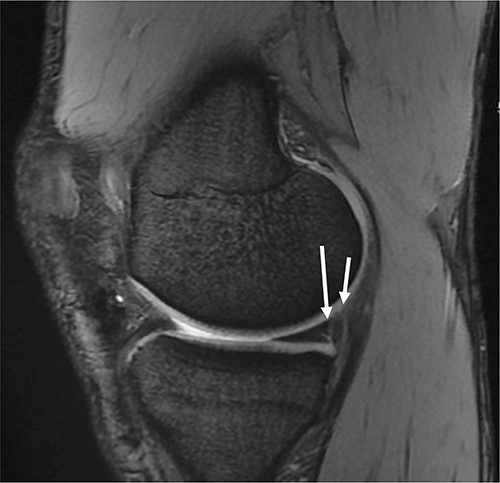

Radiography revealed normal findings. MRI revealed an intact ACL graft with proper tunnel positions. A ramp lesion was suspected based on the findings of MRI (Fig. 1).

Sagittal magnetic resonance imaging of the knee. Gradient echo sequence image of the medial compartment of the knee demonstrating a suspicious double ramp lesion. The long arrow indicates the first ramp lesion, and the short arrow indicates the second ramp lesion